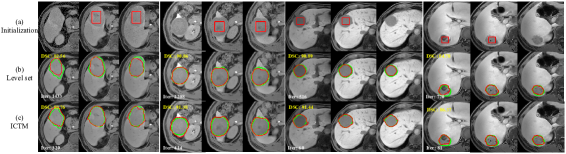

Figure 4: Zoomed examples of liver lesion MR image segmentation results. Green and red contours denote ground truths and segmentation results, respectively. Blue and white numbers at the top of images point out segmentation accuracy (DSC) and the number of iterations. Some images do not have initializations because the segmentation method is applied in a 3D manner and not all tumor slices need initializations. See Section 4.4.

4.4 Liver lesion segmentation in MR

To validate the effectiveness of our ICTM on 3D lesion segmentation tasks, we apply it to liver lesion segmentation in liver MR scans. We randomly collect 20 liver MR scans from a local hospital. Three experienced radiologists manually annotate them, and majority vote is used to generate final labels. The image sizes range from 256×256×105256256105256\times 256\times 105 to 400×400×120400400120400\times 400\times 120. The initialization of each MR scan is a cuboid inside the tumor. Figure 4 (a) shows some initialization results (red rectangle) in 2D slices. It should be noted that not all tumor slices have initializations such as the images in the first and forth columns in Figure 4 (a) because the segmentation method is applied in a 3D manner. Thus, we do not need to give initializations in each slice. In fact, only half of the tumor slices have initializations.

For fair comparison, we also apply the grid search to tune the hyper-parameters. Quantitative and qualitative segmentation results are displayed in Table 2 and Figure 4, respectively. We observe that, again, both two methods achieve similar average DSC without significant differences, indicating that the ICTM can obtain similar results to the LSM for the GAC. However, the ICTM requires fewer iterations compared to the LSM, which is about 5.655.655.65 times acceleration, implying the high efficiency of the ICTM.